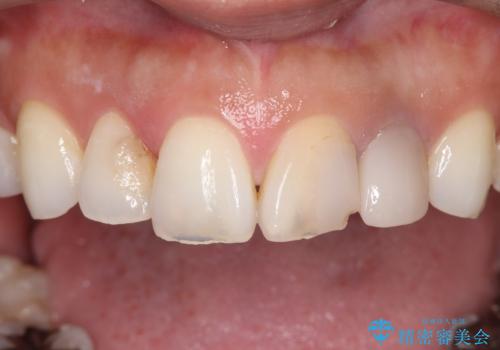

- 上顎の前歯4本が、過去の治療痕による変色や欠けで見た目が気になるとの主訴でご来院されました。患者様は、思い切り笑えるよう自然で美しい前歯を求めていらっしゃいました。そこで、最も天然歯に近い審美性を再現できるオールセラミッククラウンを用いた治療計画を立案しました。歯並びや色のバランスを整え、長期的に安定する美しい口元を獲得することを目指します。